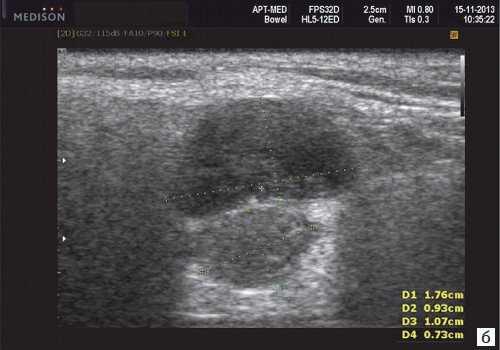

Общие характеристики при ультразвуковом сканировании

- Лучший диагностический признак на УЗИ слюнной железы - Увеличенное солидное образование околоушной или поднижнечелюстной железы

- Размер 1-5 см.

- Морфология переменная. Четко очерченные, дольчатые до инфильтративного типа края

Результаты ультразвукового исследования слюнной железы

- Серошкальное УЗИ. Одиночное солидное образование в паренхиме околоушной или подчелюстной железы. Может иметь хорошо выраженные, дольчатые или плохо очерченные / инфильтративные границы. Гипоэхогенная структура по отношению к паренхиме слюнной железы. Общее улучшение ультразвукового изображения задних структур. Иногда центральный кистозный компонент представляет некроз. Могут наблюдаться связанные аномальные интрапаротидные, перипаротидные, шейные лимфатические узлы

- Цветной допплер. Внутриузловая васкуляризация от умеренной до выраженной

Результаты КТ. Солидное образование мягких тканей слюнной железы. Повышенное напряжение по сравнению с околоушной и подчелюстной паренхимой. Изоаттенуация по сравнению с мышцами. При КТ с контрастированием однородное или неоднородное усиление ± внутренний некроз